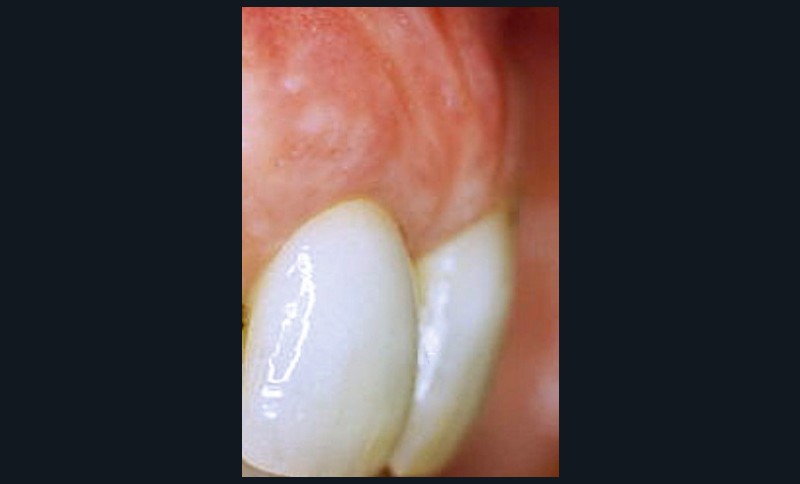

La mucosite, stade précédant la péri-implantite, se caractérise par un syndrome inflammatoire autour des implants avec des valeurs de sondage variables sans perte osseuse (fig. 2).